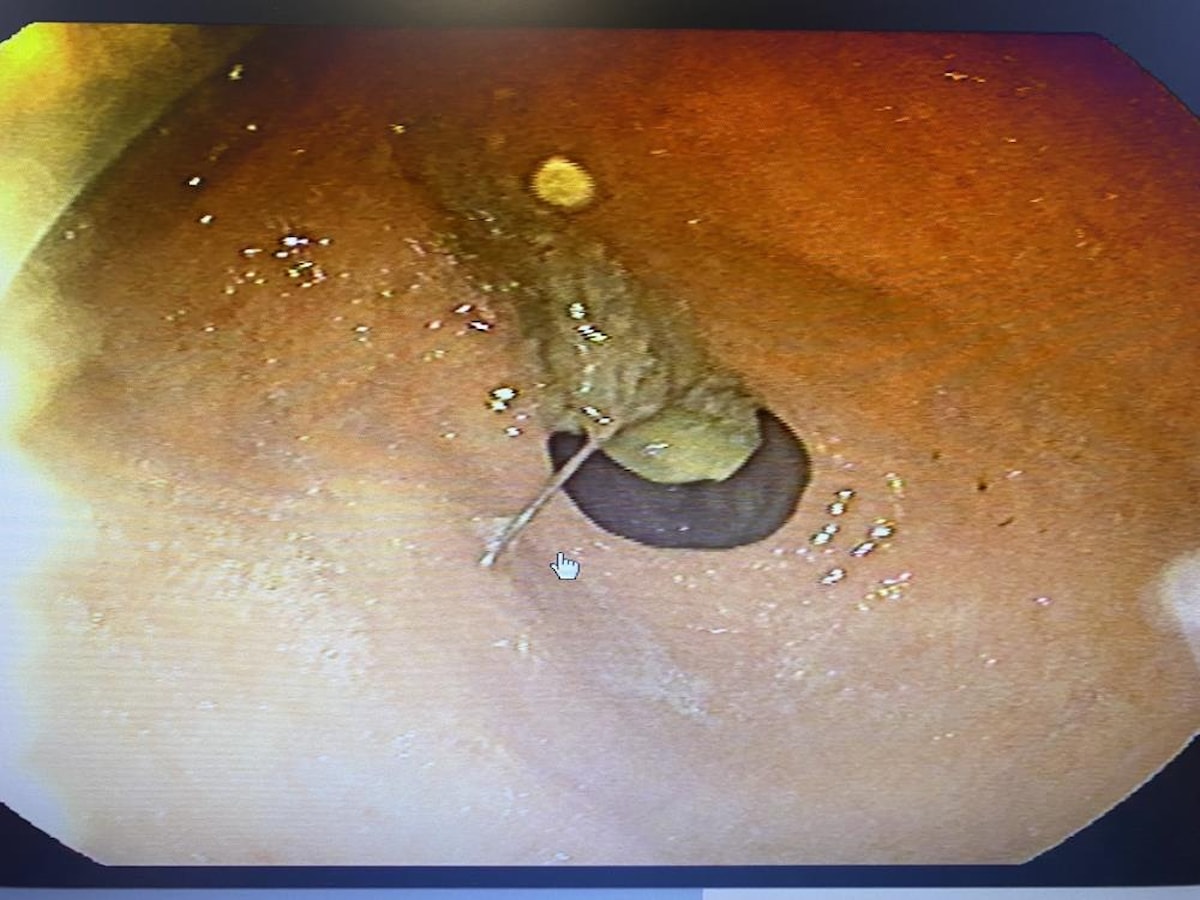

Toplu iğnenin mideye ulaştığı belirlenirken gerçekleştirilen endoskopik işlemle hastanın midesindeki iğne olduğu noktadan alındı.

“Hastamız bize geldiğinde başörtüsünü bağlamak için kullandığı iğnesini bir süre ağzına almak istediğini belirtti. Daha sonra bir hapşırma gelişmiş, aniden nefes çekme olayı olduğu için yemek borusuna bu iğne kaçmış. Bir ihtimal bu soluk borusuna da gidebilirdi böyle ani nefes almalarda o zaman soluk borusunun incelenmesi gerekirdi, akciğere kaçardı. Bu şartlarda yemek borusundan midesine doğru ilerleme olmuş. Bize başvurduğunda bu işin üzerinden 2-3 saat geçmişti, iğne yavaş yavaş ilerlemişti.

Biz acil servilerde yaptığımız görüntülemelerde iğnenin henüz daha midede olduğunu, daha fazla ileriyle gitmediğini gördük. Akabinde hastamızı endoskopi ünitemize aldık, burada yaptığımız endoskopide de tam mide çıkışında mide mukozası dediğimiz en iç tabasına saplanmış şekilde gıda artıklarının arasında durduğunu gördük. Zor da olsa özel aletlerimizi kullanarak iğnemizi tuttuk, daha sonra endoskopi kanalının içinden hastamıza herhangi bir zarar vermeden dışarıya çıkarttık. Bu iğnenin hastamıza bu aşamaya kadar herhangi bir zarar vermediğini yemek borusunda, midesinde yırtılma yapmadığını gördük.”